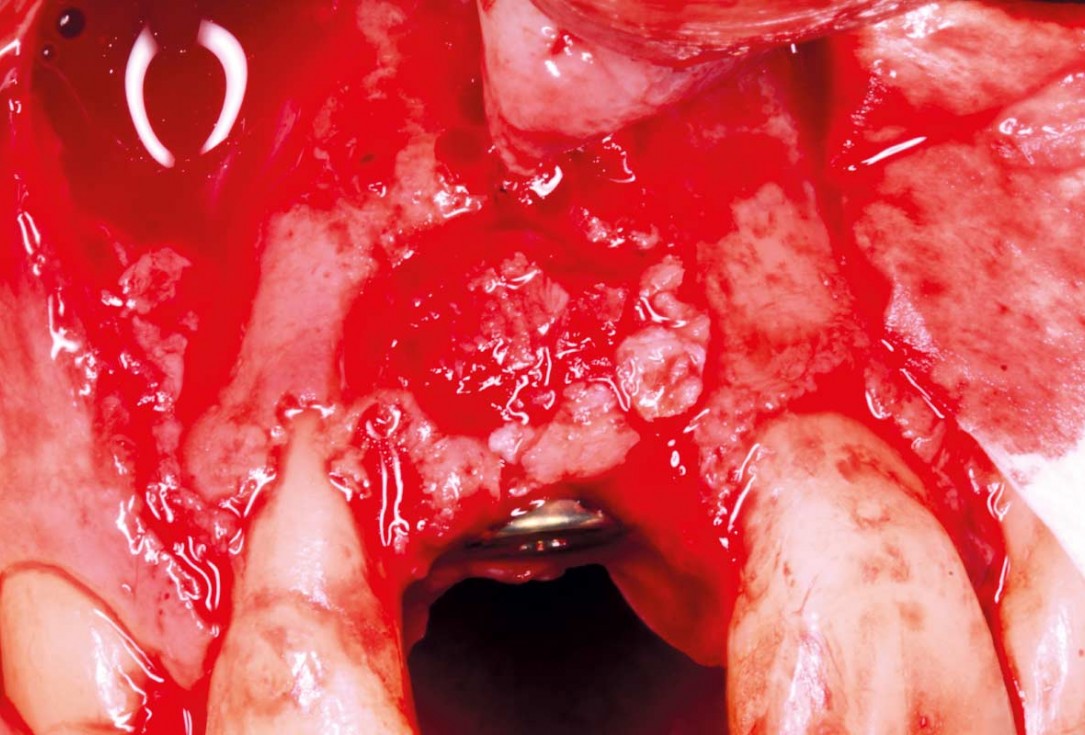

04/20 - Bone volume augmentation was conducted with maxgraft® (<2 mm mm of 0.5 cc) mixed with cerabone® (0.5- 1.0 mm) 4:1 shaped to create convexity.Delayed implant placement with GBR and soft tissue augmentation at the aesthetic area - 2 years follow up – Dr. H. Maghaireh & Dr. V. Ivancheva

05/20 - Stabilisation of Jason® membrane using additional titanium pins.Delayed implant placement with GBR and soft tissue augmentation at the aesthetic area - 2 years follow up – Dr. H. Maghaireh & Dr. V. Ivancheva